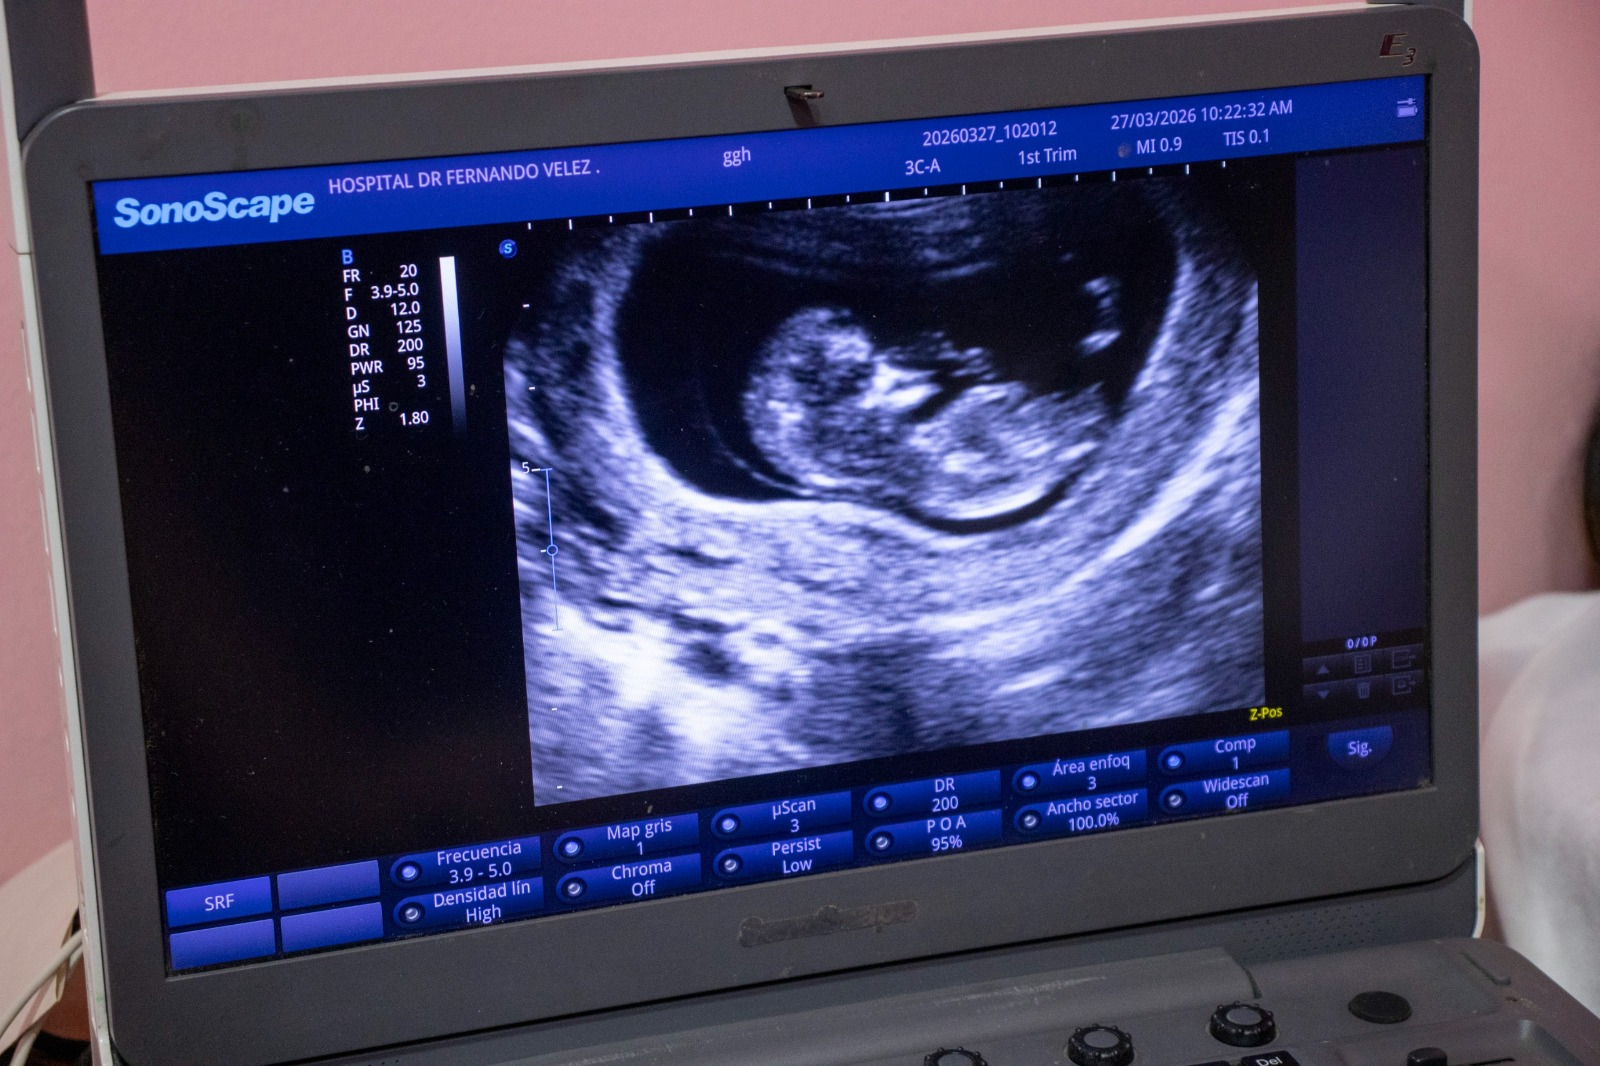

Aconsejó a las embarazadas que es importante realizarse los chequeos, porque de esa manera llevan control de cómo va avanzando el desarrollo del feto.

Kenia Mendoza González, con tres meses de embarazo, dijo que es del barrio Villa Nueva; ella también recibió atención y agradeció porque la consulta es gratuita, así como los exámenes que le hicieron en el Centro de Atención a la Mujer Dra. Ligia Altamirano.